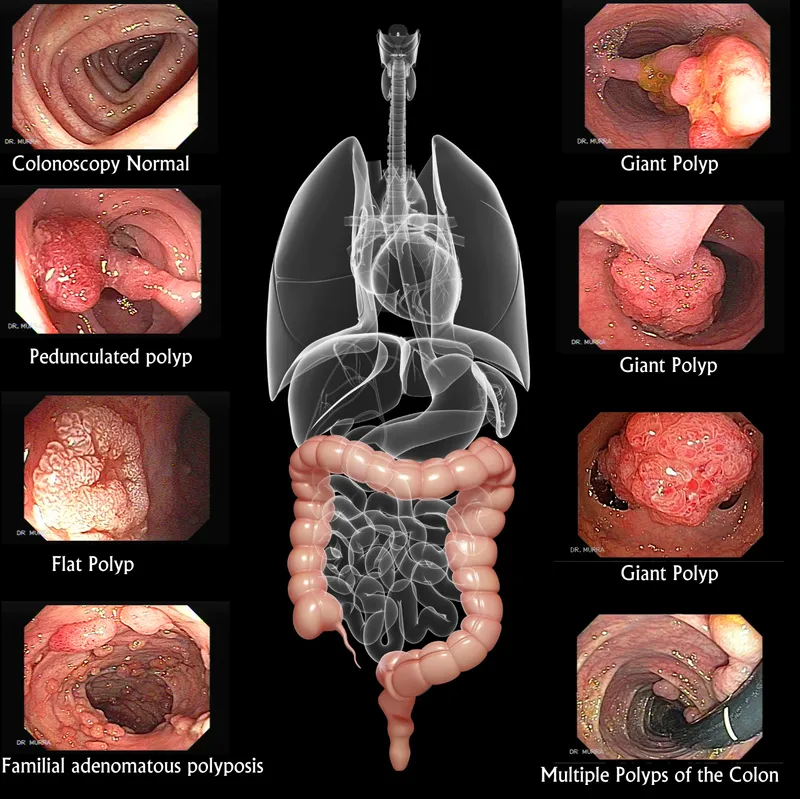

- Goal: Detect & remove precancerous polyps (adenomas) to prevent progression to adenocarcinoma.

⭐ Most CRCs arise from adenomatous polyps. Right-sided lesions often present with iron deficiency anemia; left-sided lesions cause changes in stool caliber.

- FAP: Sigmoidoscopy @ 10-12y.

- Lynch (HNPCC): Colonoscopy @ 20-25y, q1-2y.

⭐ In IBD, surveillance requires extensive random biopsies (e.g., 4-quadrant every 10 cm) as dysplasia can be flat and invisible.